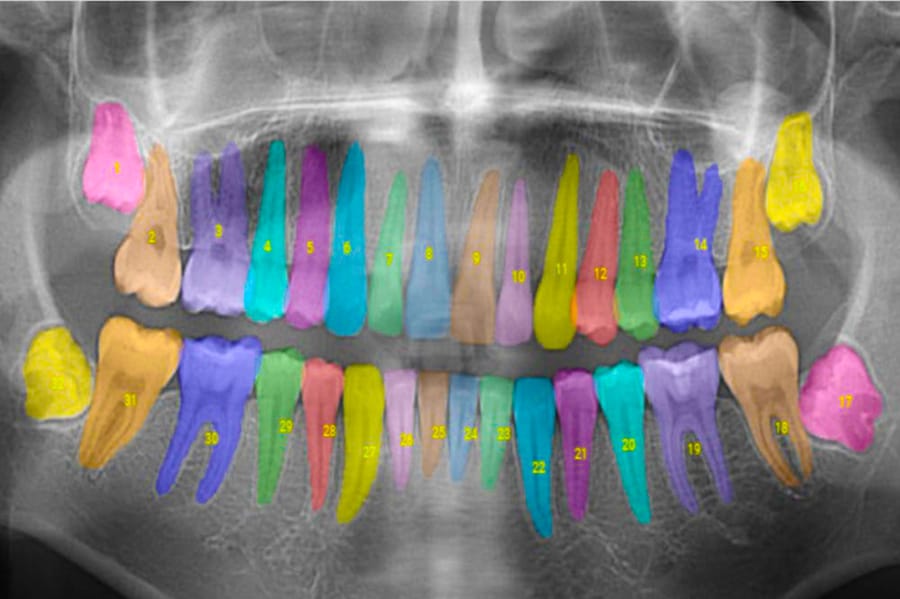

When an X-ray is imported into a computer, Overjet's software automatically provides an analysis and annotation of the image. In fact, by the time the image appears on the computer screen, it contains information about the type of X-ray taken, how the tooth may be affected, the exact level of bone loss with color overlays, the location and severity of the decay, and more.